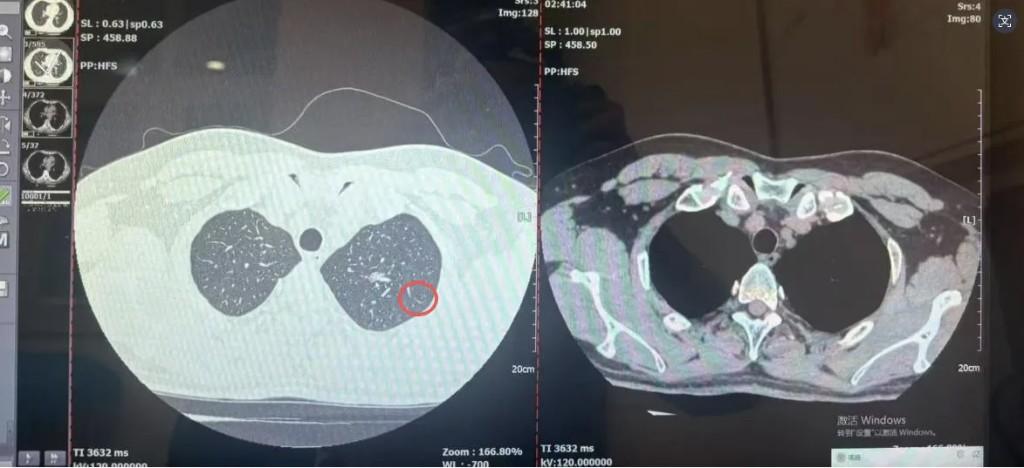

一场普通感冒引发的咳嗽,竟意外揪出肺部“定时炸弹”。41岁的刘先生(化名)因持续咳嗽就医,胸部CT检查发现左肺上叶10mm×6mm混合密度结节,西安医学院第一附属医院多学科团队(MDT)仅用72小时便完成诊断、手术,成功切除早期肺癌病灶,助其实现“临床治愈”。

据悉,刘先生平时无三高、慢病等基础疾病,此次因受凉感冒后咳嗽迁延不愈,前往西医一附院排查肺部感染。不料CT报告显示的肺结节影,让他陷入“结节是否为癌”的焦虑,饮食睡眠备受影响。一周后,刘先生参与该院肺结节多学科联合会诊,呼吸与危重症医学科、心胸外科、肿瘤内科、影像科、病理科专家共同研判:结节混合密度、形态具恶性特征,排除感染性病变可能,高度怀疑早期肺癌,且结节位置适合胸腔镜微创手术,创伤小、恢复快。